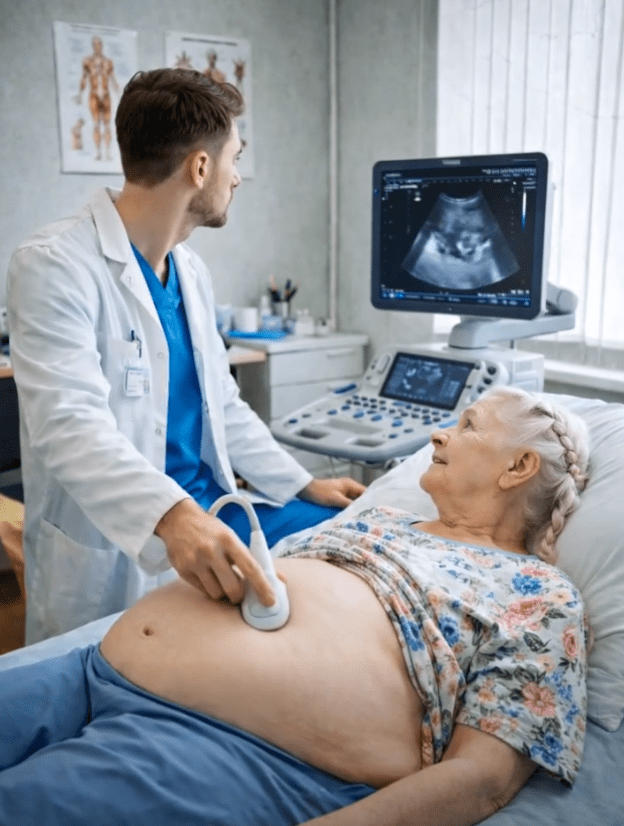

- Kako se stanje pogoršavalo, njen stomak je postajao sve izraženiji, a nelagoda sve veća. Ipak, Larisa je i dalje odbijala mogućnost da se iza svega krije nešto ozbiljno. Tek kada su bolovi postali gotovo svakodnevni, odlučila je da posjeti ginekologa. Taj trenutak bio je prekretnica, iako ona toga još nije bila svjesna.

Pregled koji je uslijedio potpuno je promijenio tok priče. Dok je Larisa očekivala da čuje potvrdu svoje trudnoće, ljekar je na ultrazvuku vidio nešto potpuno drugačije. Na ekranu nije bilo nikakvih znakova trudnoće, već formacija koja je ukazivala na ozbiljan medicinski problem. Umjesto radosne vijesti, uslijedio je šok – njeni simptomi nisu bili posljedica trudnoće, već potencijalno opasnog zdravstvenog stanja koje je zahtijevalo hitnu obradu.

- Larisa je u tom trenutku ostala bez riječi. Sve ono u šta je mjesecima vjerovala počelo je da se ruši u sekundi. Osjećaj nade zamijenio je strah, a zatim i nevjerica. Teško joj je bilo prihvatiti da ono što je smatrala novim početkom zapravo može biti signal ozbiljne bolesti. Ljekari su joj objasnili da je neophodno uraditi dodatne pretrage kako bi se tačno utvrdilo o čemu se radi, ali već tada je bilo jasno da situacija nije bezazlena.